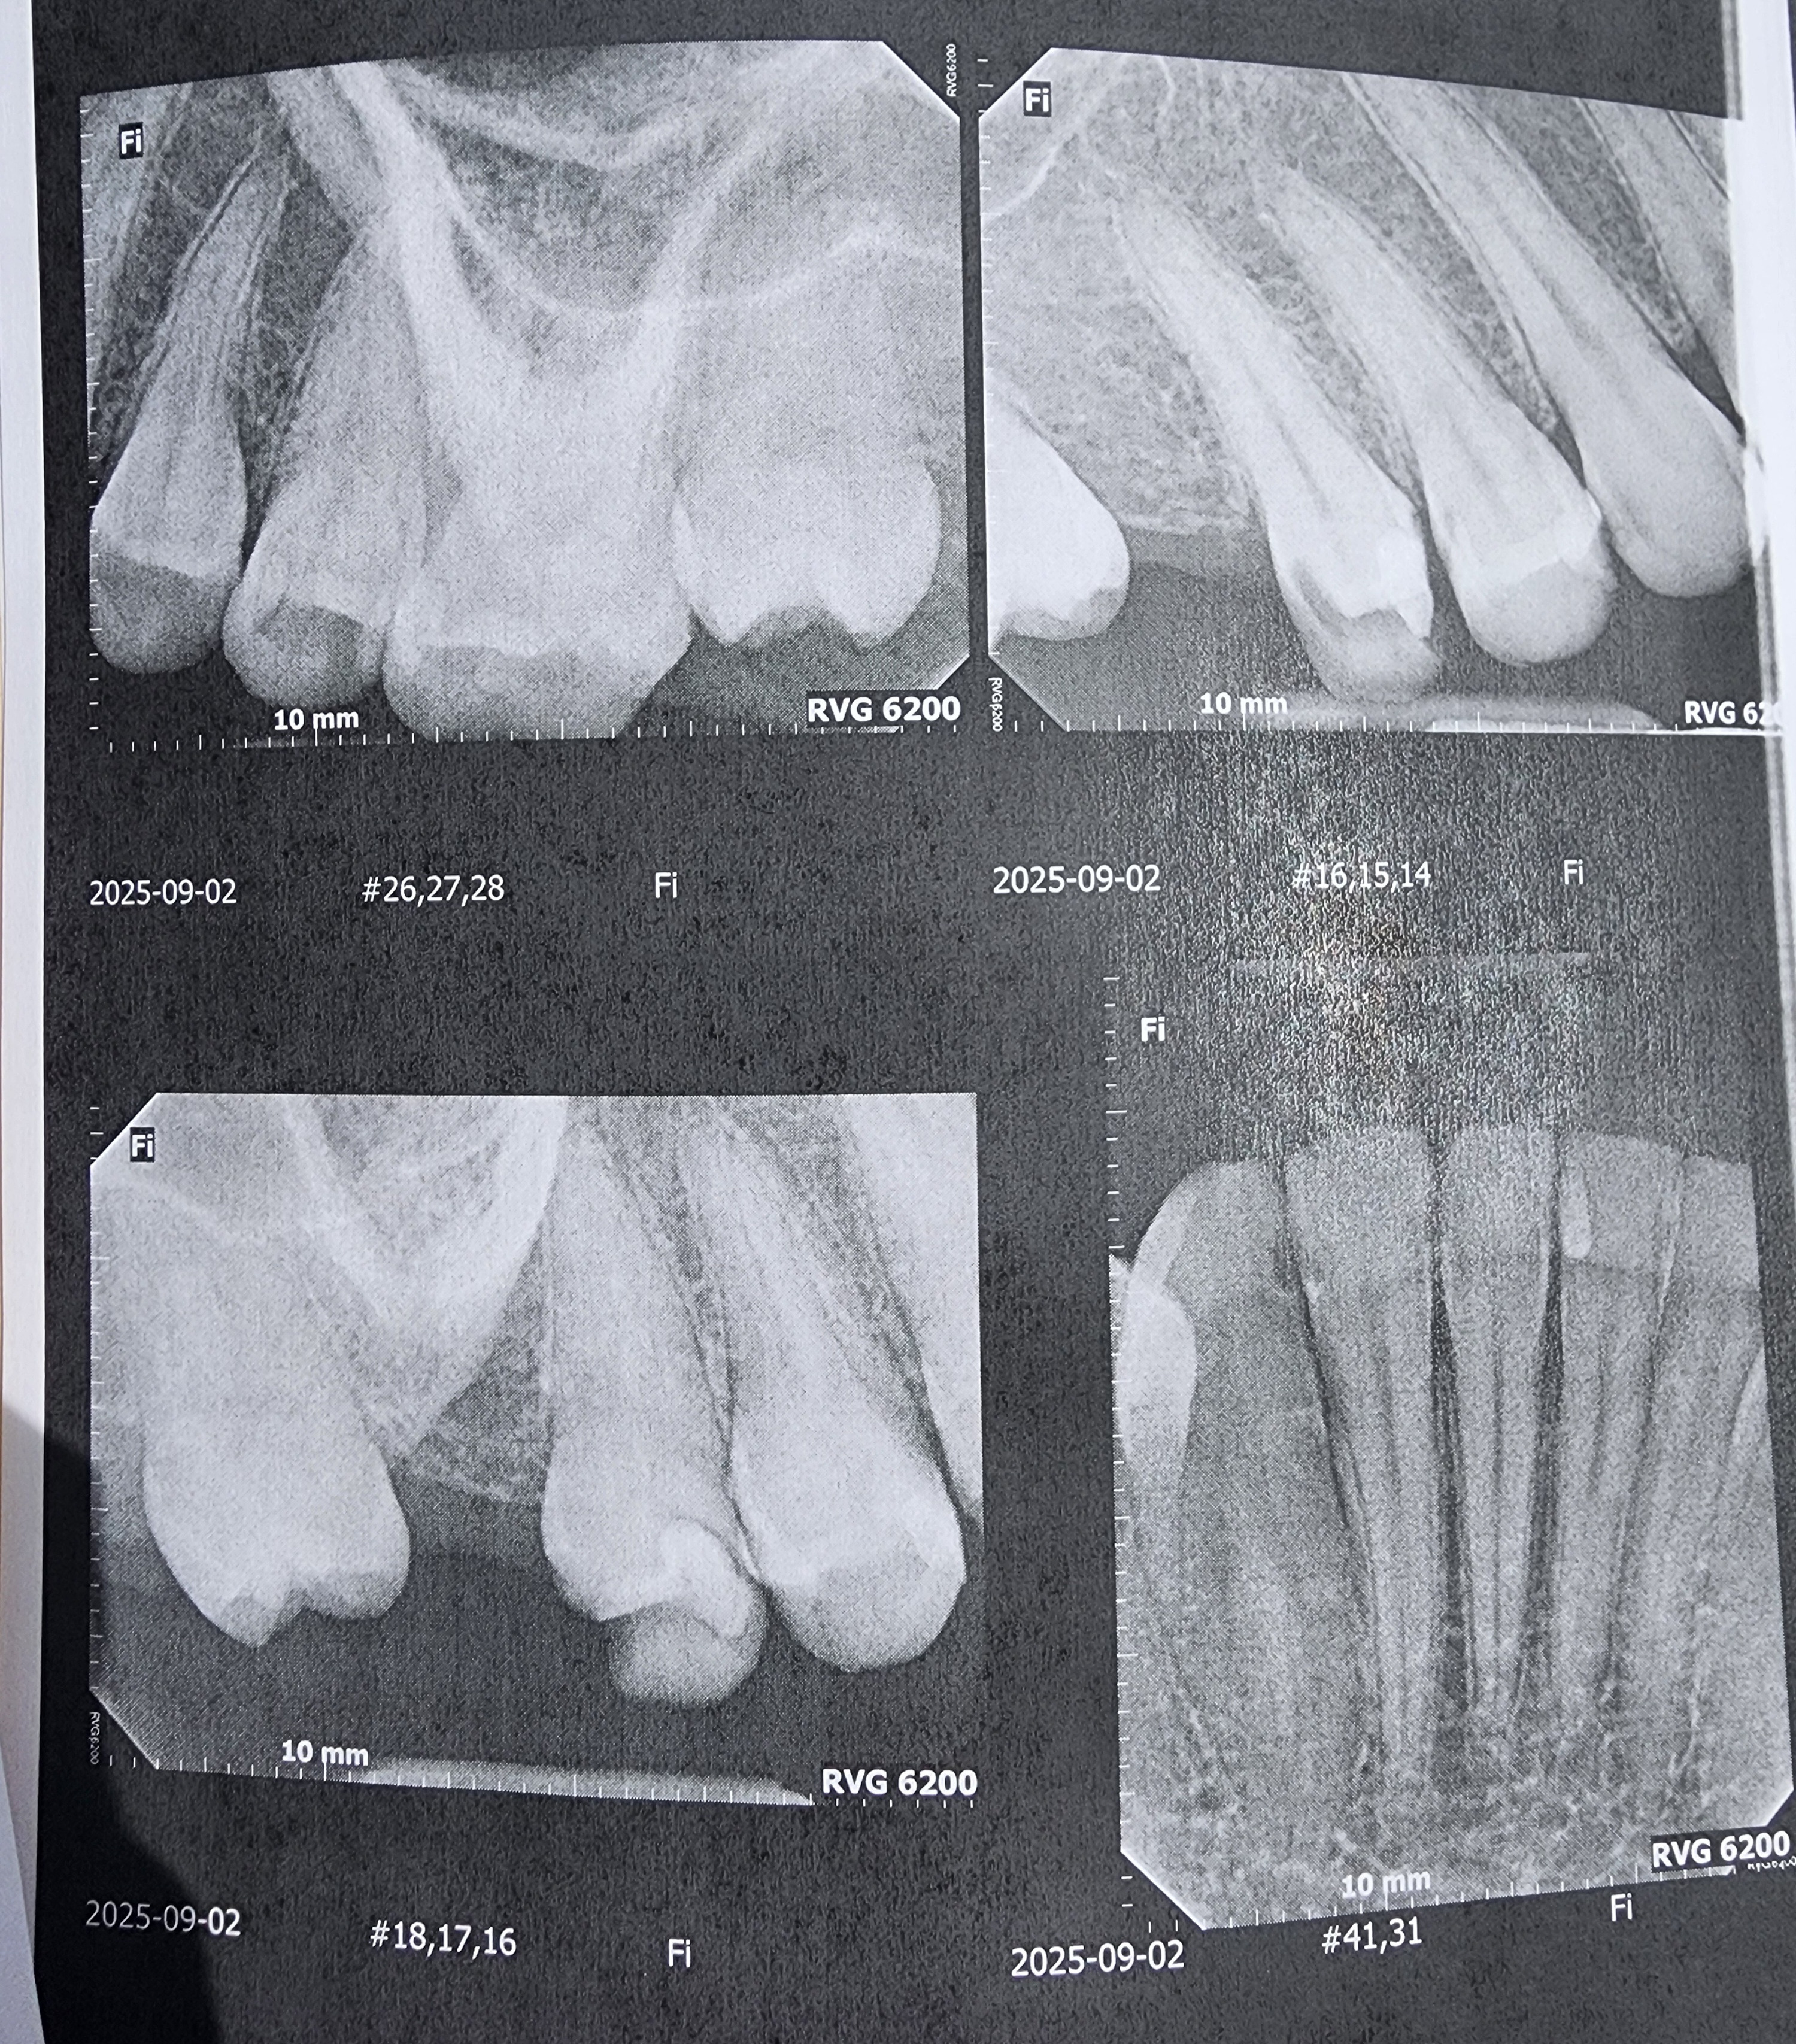

Hello. My name is Ash and those x-rays are of my not so good teeth. I knew that they weren't that good but they were worse than I could ever have imagined.

Due to an old dentist seemingly giving me bad fillings before leaving the practice, it seems I need 4 Crowns, 1 or 2 Root Canals, and a whole ton of fillings. I was prepared for a couple thousand but it seems they want about 12,400 in total. And this includes a dental plan card they let me sign up for to half the entire bill. They want me to pay before each appointment and at this point I dont know what I can do.

I am making this gofundme to at least get 12,000. this will cover the worst tooth that needs both the crown and root canal, the crowns, and all of the cavities. I have family willing to lend me the other 500 or so to get the cleaning done.